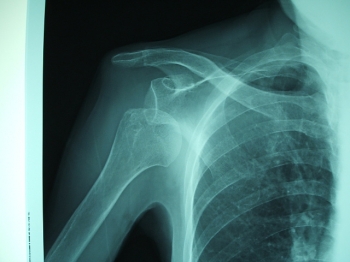

1位 肩脱臼